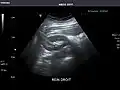

Abdominal Ultrasound (Full Exam)

STRUCTURED REPORT

(Technique: Transabdominal ultrasonography; Device: Toshiba Aplio XG)

Liver: Diffusely homogeneous and normal in echogenicity. No focal mass or contour nodularity. No intrahepatic biliary ductal dilatation.

Portal Vein: Patent main portal vein.

Gallbladder: No stones, wall thickening, or pericholecystic fluid.

Common Bile Duct: Nondilated measuring 1.3 mm at the level of the porta hepatis.

Pancreas: Visualized portions unremarkable.

Spleen: Normal in size.

Kidneys: Right and left kidneys measure 11.5 cm and 12 cm in length respectively. No hydronephrosis. Small left lower pole kidney cyst.

Ascites: None.

Aorta: Visualized portions normal in caliber, 16 x 15 mm.

IVC: Normal.

IMPRESSION:

Normal abdominal ultrasound.

Right kidney -